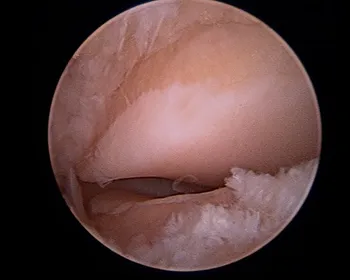

Intraoperative subtalar joint arthroscopy pics

Scar tissue at the middle facet

Cleaned out middle facet